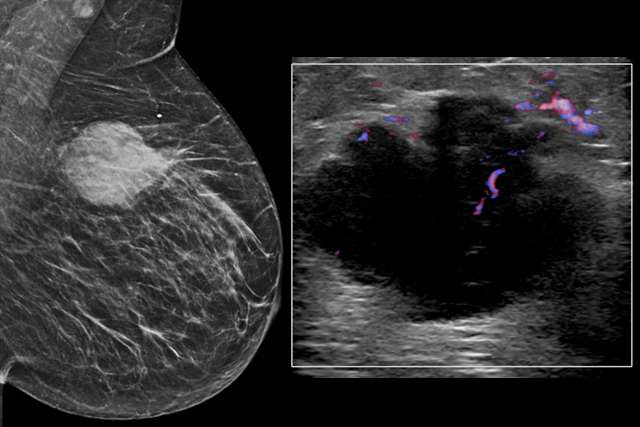

BIRADS:

Mammography

Ultrasound

Learn how to use BI-RADS terminology to interpret Mammograms, MRIs, and Ultrasound cases.